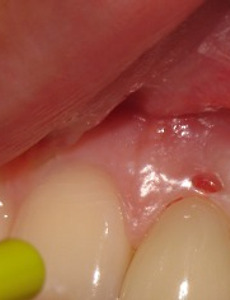

잇몸이 붓고 아플때 무슨 병일까 잇몸이 붓고 아플때 무슨 병일까 치육염과 치주염을 합해서 부르는 치주병은 잇몸이 붓고 가끔은 피가 나는 증상을 보이고 있습니다. 치육염이 가벼운 치주염으로 발전하고 이것이 증상이 계속 진행되면서 결국에는 이가 흔들리는 지경에 이르게 됩니다. 치육염의 단계에서는 그다지 심하게 통증을 느끼지는 못하지만 그냥 방치하면 점점 더 증상이 진행되면서 이가 흔들리게 되는데요, 그렇기 때문에 잇몸이 붓고 하는 그 단계에서부터 치주병 초기증상이라 생각하고 치료해 주어야 합니다. 잇몸이 붓고 아플때 까지 가면 중간 이상의 단계에까지 이른 것입니다. 잇몸에서 생기는 문제 중에서 가장 많이, 흔하게 볼 수 있는 증상은 바로 잇몸이 붓고 아프다는 증상입니다. 그리고 이런 증상을 계속 방치하면 이가 흔들리고 그러다가 빠지거나 약.. 2019. 12. 18.